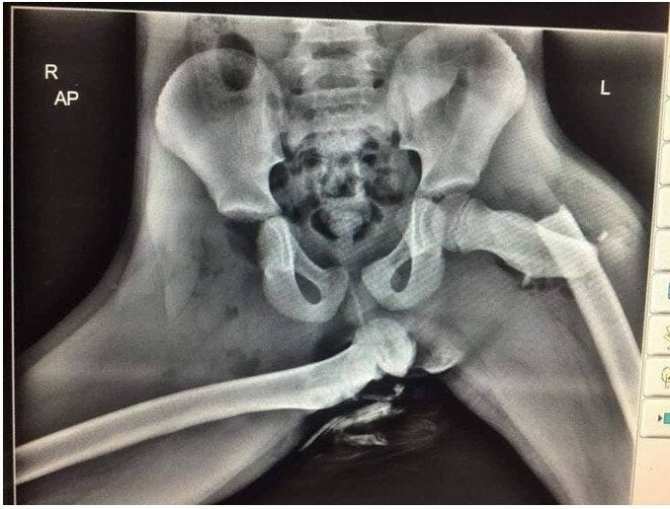

8. Этот рентгеновский снимок участника трагедии демонстрирует, почему нельзя класть ноги на приборную панель